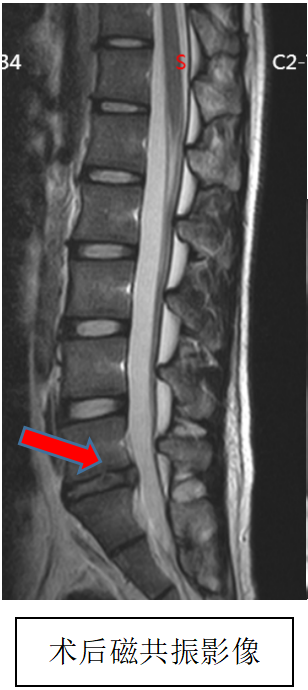

吴静晔主任是北京积水潭医院派驻郑州医院的脊柱外科专家,也是北京积水潭医院郑州医院脊柱外科的执行主任,在为小明做了全面检查后,结合术前 MRI 精准定位病变部位,在充分沟通诊疗方案与风险后,为小明实施了微创手术,精准解除神经压迫。

术后即刻复查磁共振显示,手术达到预期效果,小明的疼痛快速缓解,麻木感逐渐消退,终于能正常坐立、平稳走路。

在医护团队的康复指导下,他慢慢恢复了肢体力量,重新找回了青少年该有的活力,也能回归正常的学习和生活。